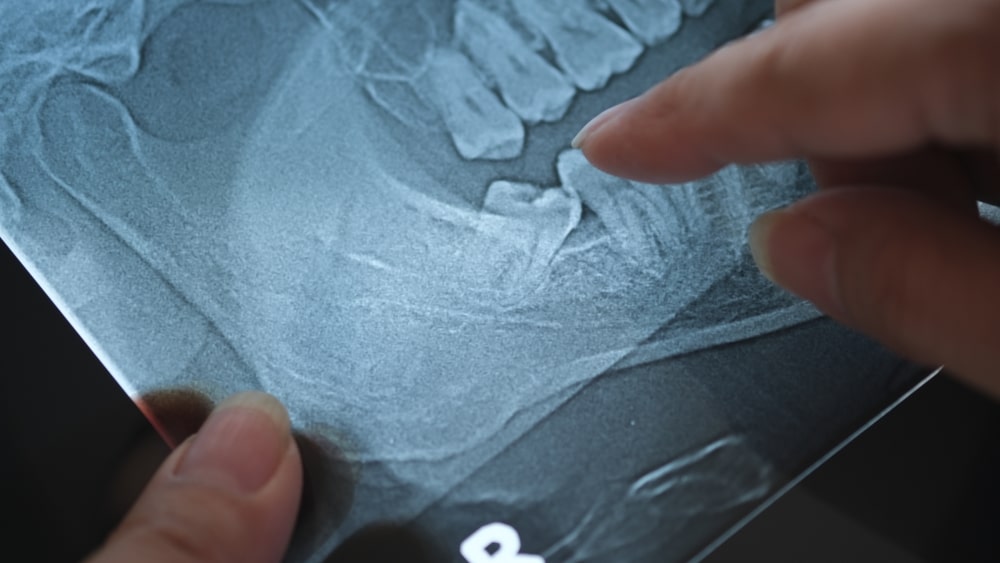

In many cases, wisdom teeth are removed preventively — even before symptoms arise — especially if X-rays show they’re growing in at an angle or unable to erupt properly.

Your dentist will start with a detailed evaluation, which may include digital X-rays or cone beam 3D imaging to determine the exact position of your wisdom teeth. Depending on your specific case: